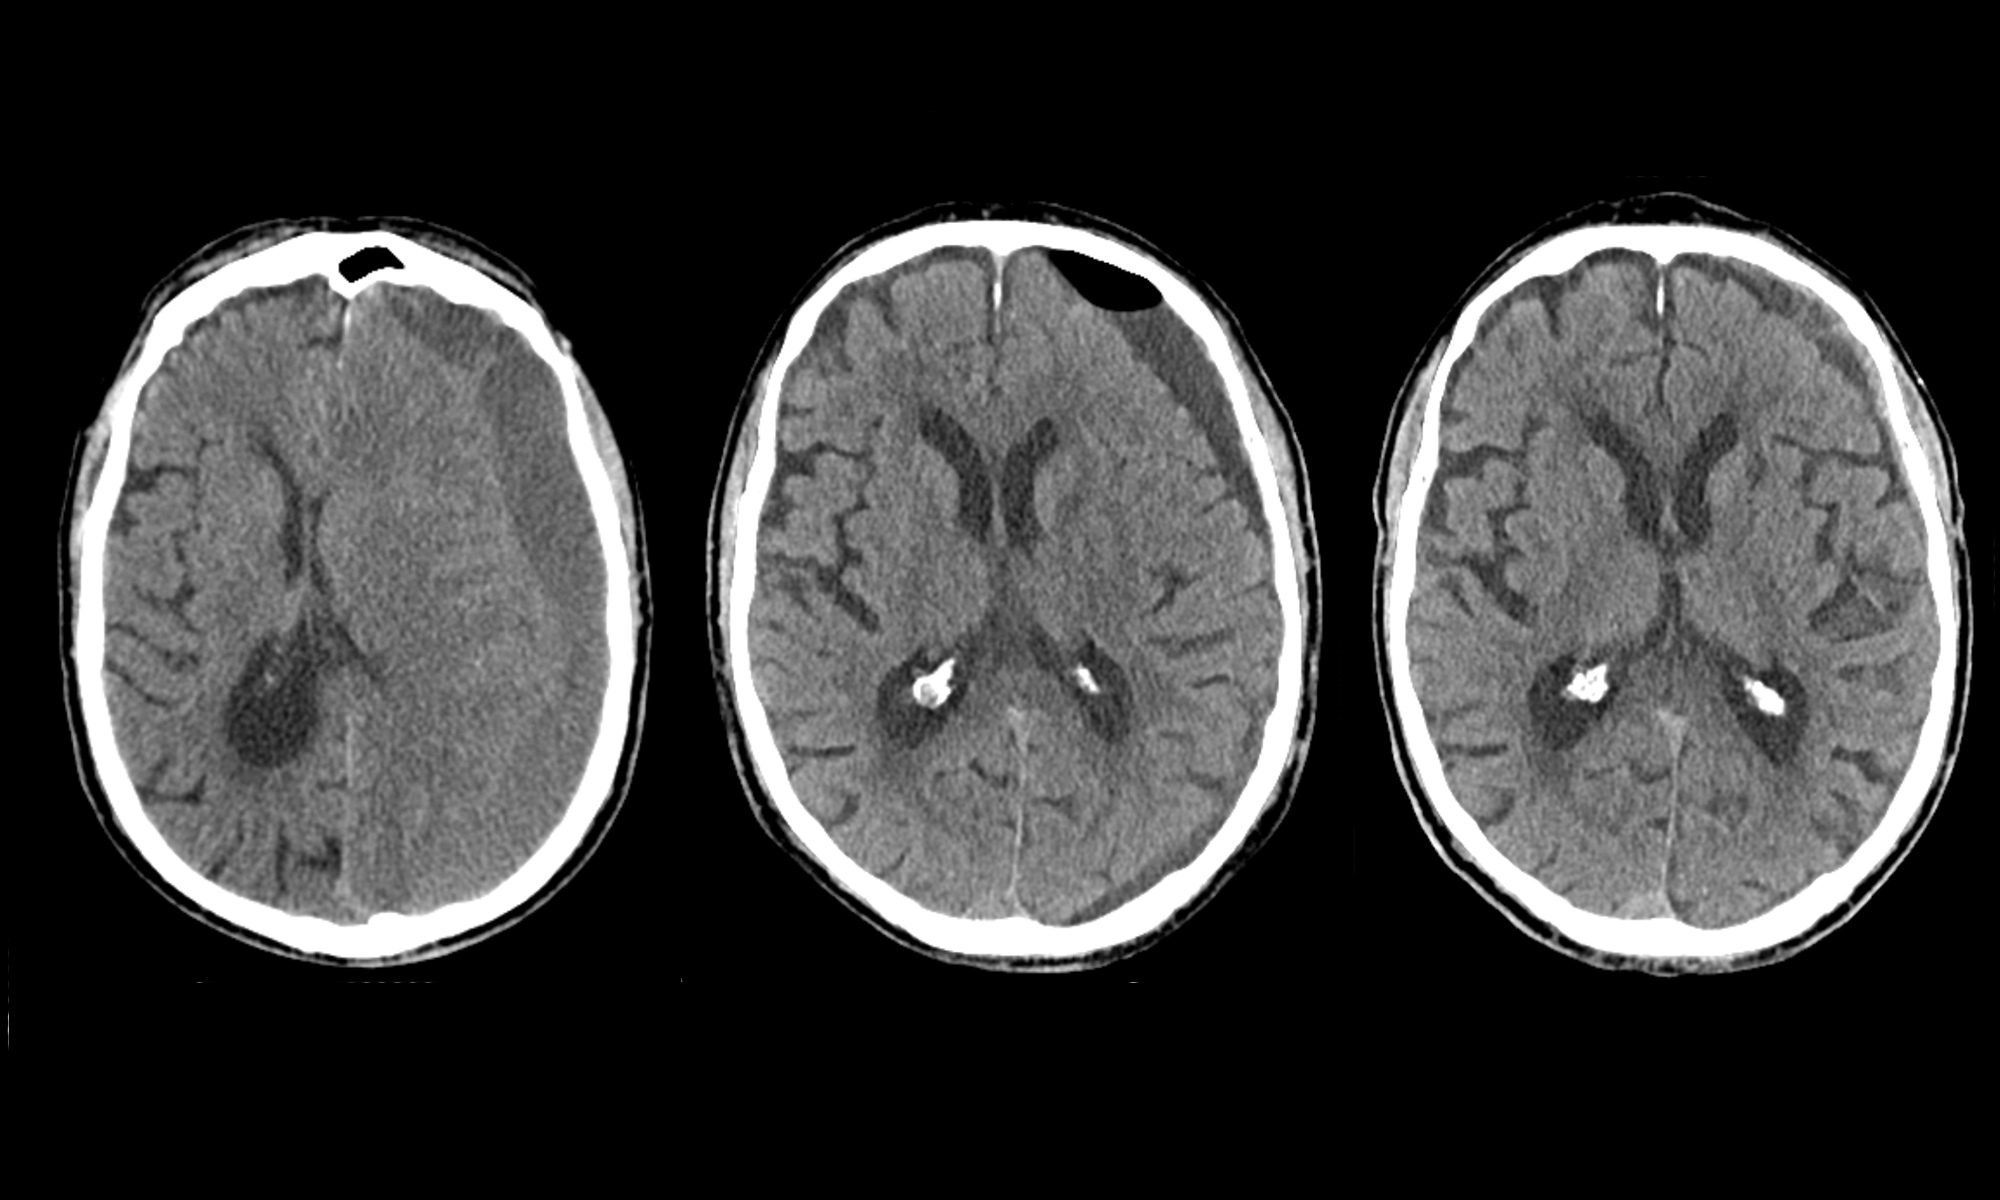

Chronic subdural haematoma is bleeding between the brain and the skull, the intracranial space, usually following a head injury. It occurs predominately among elderly people who take a blood thinner. The blood can be drained with a relatively simple surgery involving two small burr holes, and approximately 80% of the patients are cured. Despite surgery, recurrent bleeding occurs at the same place among a minority of patients, and surgery must be repeated a few days or weeks thereafter. In order to discern whether a second surgery is needed, a computed tomography (CT) scan is usually performed to determine how much blood remains between the brain and skull after surgery. Researchers at the University Neurocenter Bern at Inselspital have questioned how well these images in general serve to predict the need.

Lead author Prof. Dr. med. Philippe Schucht explains the results: “When we make a CT scan after surgery, basically all patients still have blood around the brain. As the attending physician, it is tempting to perform a second surgery to achieve a ‘better’ result and also prevent recurring ailments for the patient. In most patients, however, this residual blood is resolved by the body with time, which is why it is difficult to predict whether another surgery is needed later. In the event that the bleeding gradually increases, those affected will experience headaches or weakness again. Then we still have time to examine and perform a CT scan – but only when it is truly necessary.”